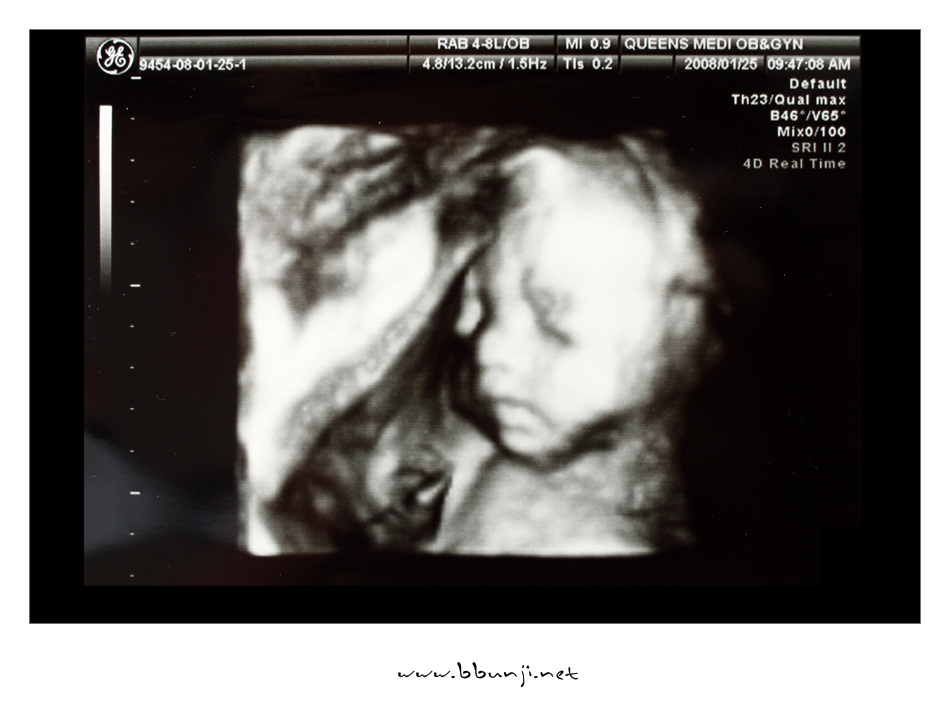

사랑이… 24주 째.. *^^*

2008년 01월 25일

이번에 입체 초음파 한다고 어찌나 기대를 하고 갔는지~~

얼굴 가리고 다리 움직이고 초음파 하면서도 막 움직이는게 너무 희안합니다.

코도 오똑한거 같고 입술도 이쁘게 생겼고…

얼굴 갸름한거랑 발 모양은 엄마 닮은거 같고 손가락도 긴거 같고 ㅋㅋㅋ

이번에는 갔더니 길이는 초음파에 한번에 안 잡혀서 알 수 없고 몸무게는 760g 정도 나간다고 하더라구요.

주수에 맞게 아주 잘 크고 있다고 초음파 사진보니 그나마 얼굴에 살이 조금 붙은듯…